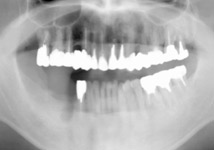

| 長年放置していたために、噛みにくい状態が続き食事がしにくかったところを、左上の奥と右上の奥にインプラントを入れて噛めるようになりました。今ではよく噛めると喜んでいらっしゃいます。 |

|